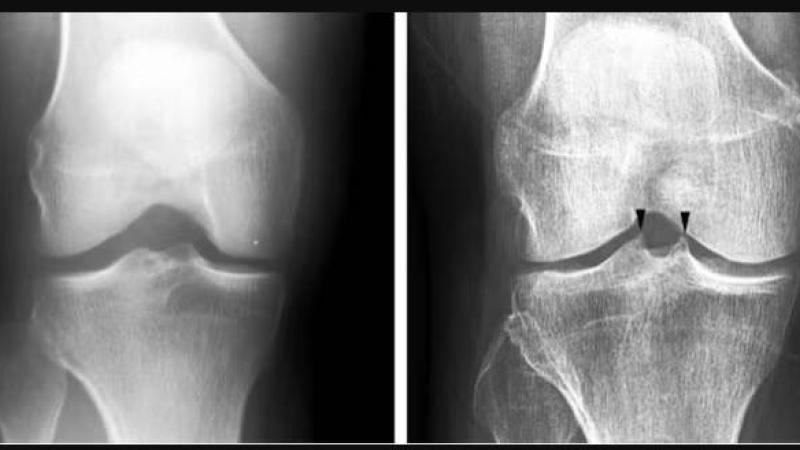

ويصيب التهاب المفاصل التنكسي ربع البالغين، وينجم عن تآكل الغضروف الذي يبطن أطراف العظام، ما يؤدي إلى الشعور بالألم والتصلب وصعوبة الحركة، ولا يتوفر علاج، بخلاف أدوية تخفيف الألم، وصولاً إلى استبدال المفصل.

وأوضح: «كشفت النتائج، أن إجراء تعديل فردي بسيط على زاوية القدم أثناء المشي، أدى إلى تخفيف كبير في الألم، وتحسين في صحة الغضروف، كما أظهر التصوير بالرنين المغناطيسي تباطؤاً في تدهور الغضروف لدى من خضعوا لهذا التعديل».